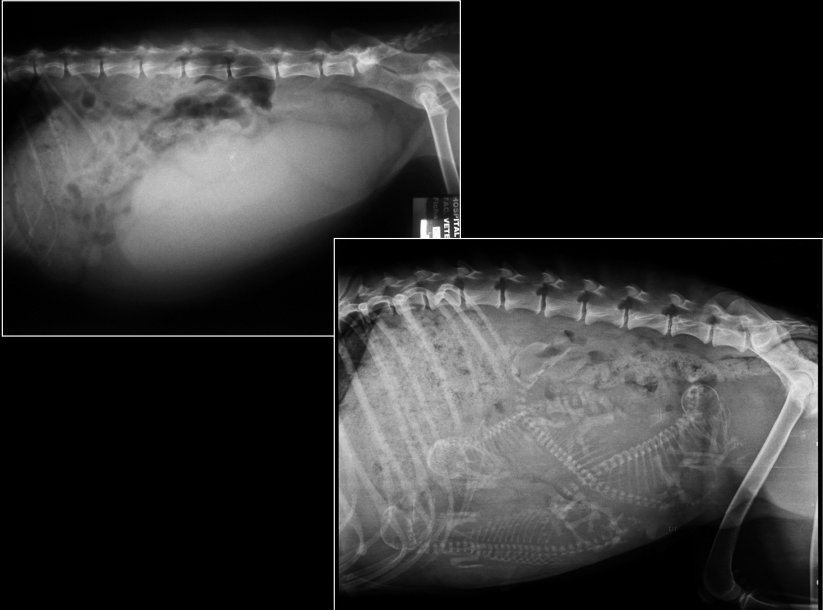

ÚTERO

- Normalmente no se ve.

- Visible cuando distendido: estructuras tubulares tortuosas en abdomen caudoventral.

- Causas:

- Fisiológico: gestación temprana

- Patológico: piómetra, hidrómetra, mucómetra, neoplasia, absceso de muñón

- Gestación: mineralización fetal visible 40–45 días.

- Muerte fetal (Si encontramos gas con los fetos), momificación, distocia (Problemas para el parto).